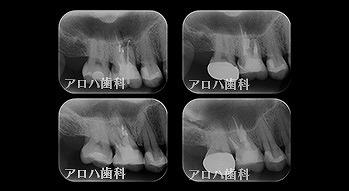

外科的歯内療法

case8

自費の補綴

頬側に瘻孔

case9

遠心口蓋側に限局性の深いポケット

上顎洞に波及している。

case10

左上に腫脹、圧痛。

根尖部に透過像

術前、術直後、予後

術前、術後